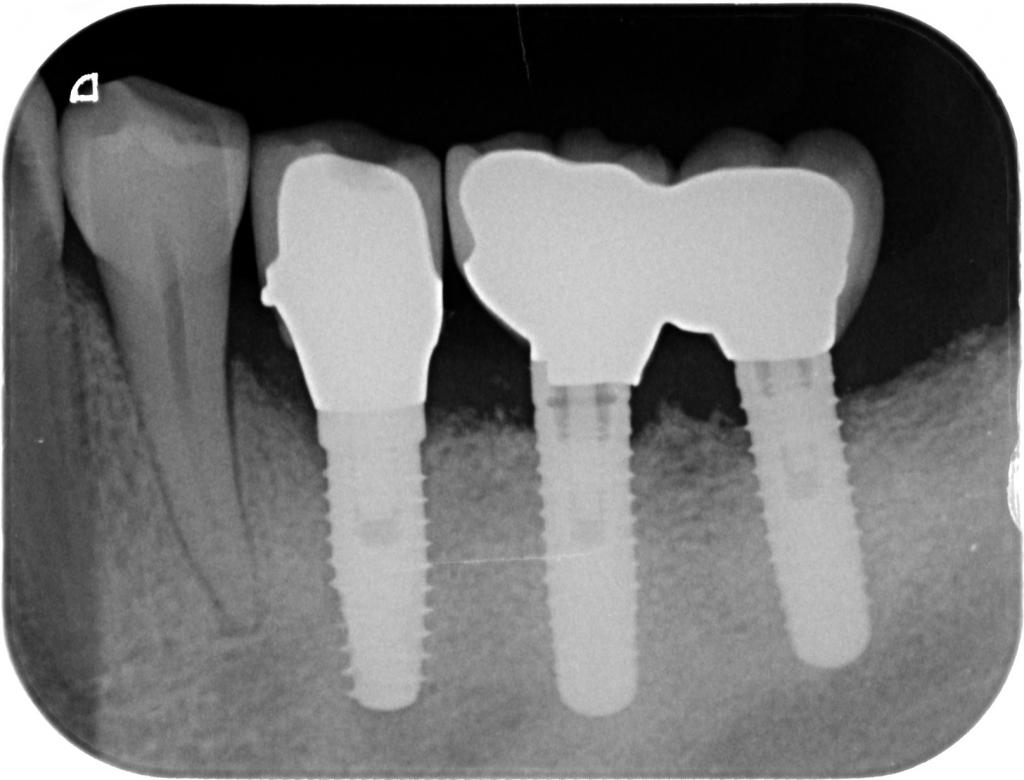

- 術後のレントゲン写真です。

20年ほど前に行ったインプラント部も骨の吸収も見られず、問題なく機能しています。